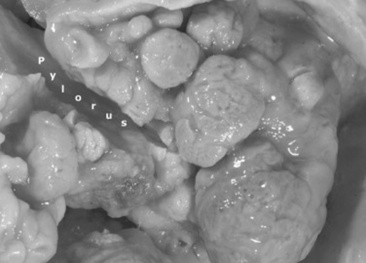

Abdominal radiography is useful to evaluate the small and large intestines for sand accumulation, enterolithiasis, impactions, or small intestinal disorders in foals. When sand is ingested, it generally will accumulate within the large colon along the ventral abdomen8 (Fig. 32-4). Radiography has been found to be a useful method to monitor the resolution of sand impactions after medical management; however, sequential examinations are needed to verify that the volume of sand has reduced.8 If the volume of sand is large enough, it is difficult to determine if an enterolith is present because of summation of the two lesions. Enteroliths are a solid concretion of mineral that usually forms around a nidus, such as a metallic foreign body (Fig. 32-5). The mineral composition is varied, as illustrated by the different opacities present within the enterolith. Radiographs have a 96.4% positive predictive value to detect enteroliths in high-prevalence areas. These enteroliths were generally found to be within the midabdominal radiograph, and 67% of small colon enteroliths caused large colon distention, which was also identified on radiographs.7 Impactions are more difficult to diagnose because usually there is just increased feed accumulation within the abdomen. Although no enterolith or obstruction is identified, granular material can be seen, usually within the ventral colon near the sternal flexure. This is because pelvic flexure impactions will cause the feed material to accumulate orad, causing distention of the left ventral colon (Fig. 32-6). Intestinal disorders such as functional ileus secondary to enteritis (Fig. 32-7) or obstruction secondary to intussusception or meconium impaction (Fig. 32-8) in foals can also be identified on abdominal radiographs. These images show large dilation of the small intestine, and differentiation between functional and mechanical ileus in foals is generally based on the size of the intestine and the volume of gas that is present.9 Evaluation of the abdomen using ultrasound may aid in qualifying the small or large intestinal motility as well as identifying the source of an obstruction if the determination on radiographs cannot be made.

image

Fig. 32-5 Radiograph of enterolith obtained after surgical removal from the small colon. Note the variation in opacities caused by the various types of mineral that are contained within the enterolith.